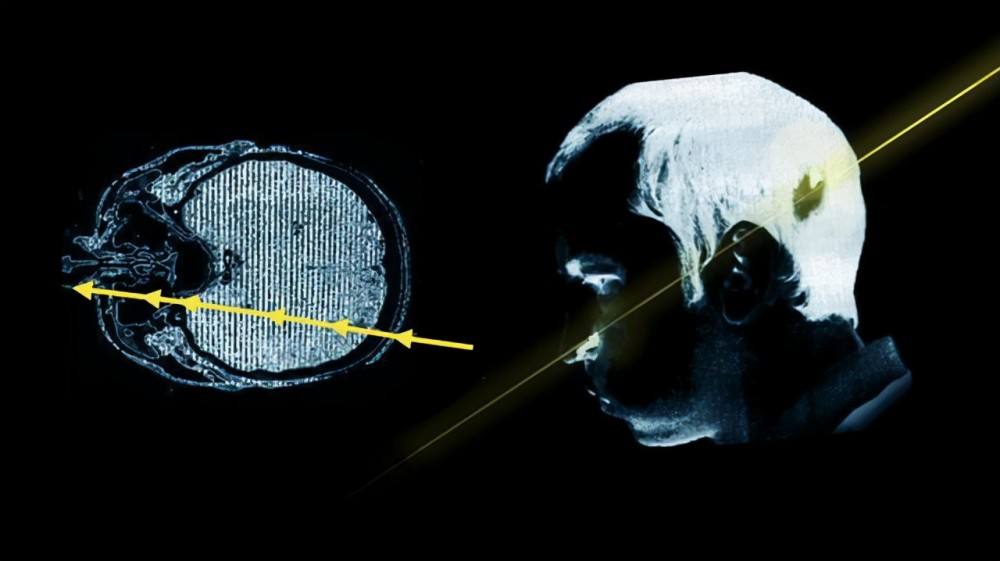

在这位物理学家将头探进去的一刹那,还在管道内以接近光速运行的高能质子束瞬间从他的左后脑穿到了左脸。

这个高能质子束大约包含十的十二次方数量级的高能质子脉冲,其携带的辐射高达20万拉德,从理论上来说,只有被轰击的左半边脸无法再控制,成了永久性面瘫,最重要的是,这束贯穿他大脑的质子束没有损伤他的质量,出院不久后他就拿到了博士学位。